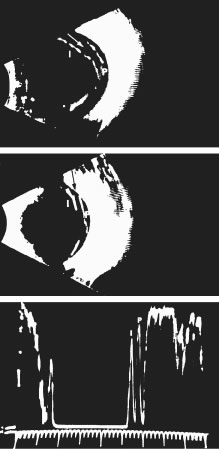

Oksala, among the first to employ B-scan ultrasonography to image vitreous in the late 1950s and early 1960s, summarized his findings of aging changes in 1978.175 In that report of 444 “normal” subjects, Oksala defined the presence of acoustic interfaces within the vitreous body as evidence of vitreous aging and determined that the incidence of such interfaces was 5% between the ages of 21 to 40 years and was 80% in individuals older than 60 years of age. In clinical practice, however, only profound entities such as asteroid hyalosis, vitreous hemorrhage, and intravitreal foreign bodies (if sufficiently large) are imaged by ultrasonography. At the vitreoretinal interface, the presence of a PVD is often suspected on the basis of B-scan ultrasonography but can never be definitively established, because the level of resolution is not sufficient to reliably image the posterior vitreous cortex, which is only a little more than 100 μm thick at its thickest portion. However, recent studies have successfully used this technique to determine the presence of a split (Fig. 11) in the posterior vitreous cortex, called vitreoschisis, in patients with proliferative diabetic vitreoretinopathy.176 The success achieved in using ultrasound to identify this important pathologic entity probably results because in advanced cases this tissue is significantly thickened by nonenzymatic glycation of vitreous collagen and other proteins177 in the posterior vitreous cortex. Future studies should determine if vitreoschisis can be identified by ultrasound in other conditions, especially premacular membranes with pucker and macular holes. However, it may turn out that the thickness of these tissue planes is below the level of resolution presently available with ultrasonography. Thus, it follows that the diagnosis of complete PVD cannot be reliably established by ultrasonography.

Fig. 11. Vitreoschisis. B-scan ultrasonography of vitreoschisis demonstrates splitting of the vitreous cortex (arrow) that can mimic posterior vitreous detachment. In diabetic patients, blood can be present in the vitreoschisis cavity.176 (I, inner wall; P, posterior wall of vitreoschisis cavity within the posterior vitreous cortex) (Photograph courtesy of Dr. Ronald Green. From Green RL, Byrne SF: Diagnostic ophthalmic ultrasound. In Ryan SJ (ed). Retina. St Louis: CV Mosby, 1989.)